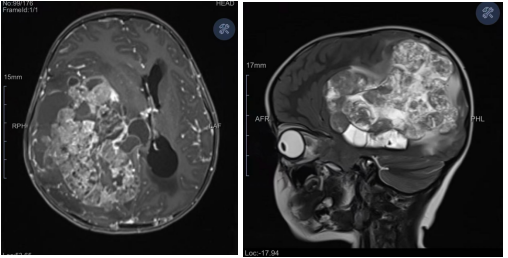

“患儿右侧大脑内长满了肿瘤,最大直径达13公分!”看着轩轩的影像检查资料,儿童神经外科主任医师王超心中一紧。影像结果清晰显示,巨大的瘤体已严重压迫患儿正常脑组织,且已形成脑疝,随时可能夺走孩子的生命,病情危急万分。

尽管患儿脑肿瘤体积巨大,手术难度极高、风险系数极大,但在王超眼中,这是一场不容有失的生命保卫战。凭借丰富的临床经验和精准的病情判断,王超明确:孩子仍有一次性全切肿瘤的希望。